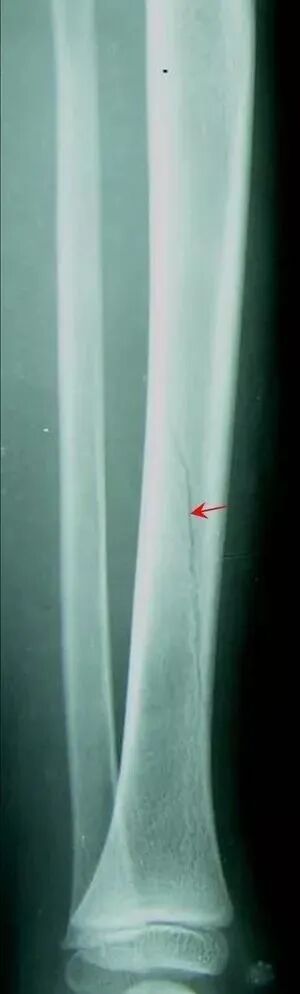

【普通放射图片】:

【影像表现】:X线平片显示胫骨不完全性骨折裂,骨折线不明显。

【影像诊断】:胫骨青枝骨折。